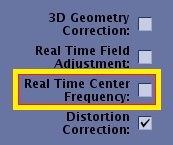

Real Time Center Frequency

The Real Time Center Frequency option is available with DW-EPI scans, DTI scans (DW-EPI scans with Tensor selected as the Diffusion direction) and 2D FSE Fat SAT scans (2D FSE with Fat Saturation). In DW-EPI and DTI scans, Real Time Center Frequency applies the optimal center frequency for each slice. In 2D FSE Fat SAT scans, when the option selected on, dynamic center frequency and shim will be applied for each prescribed slice to improve fat saturation performance.

The Real Time Center Frequency option is located on the Details tab for DWI and DTI scan prescriptions.

Figure 2. Real Time Center Frequency on/off affects on fat suppression

Table 1. Image legend Number Description 1 Image acquired with Real Time Center Frequency option turned Off. The arrows indicate the area of poor fat suppression.

2 Image acquired with Real Time Center Frequency option turned On. Note the improved fat suppression. - To reduce signal drop-off in areas of high B0 inhomogeneity (off-isocenter, or area with high tissue susceptibility).